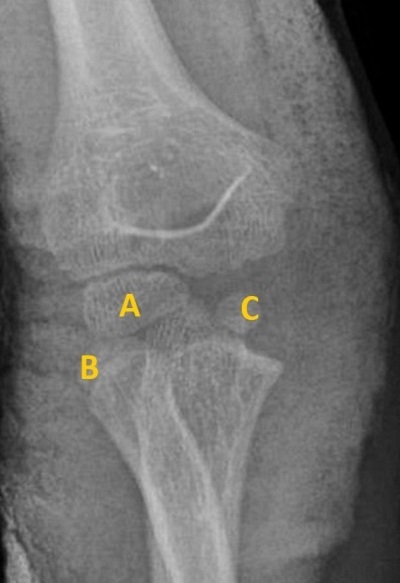

1. Paciente de 9 años que presenta dolor del codo derecho tras caída. Presenta tumefacción y dolor a la movilidad. En la radiografía (Figura 3) no se encuentran líneas de fractura. Se diagnostica a los 5 días de fractura de epitróclea.

Figura 3. Fractura de epitróclea

A: capitellum; B: cabeza de radio; C: tróclea; D: epitrócela avulsionada; E: olécranon.

En la radiografía se encuentran el capitellum y cabeza del radio, pero no se identifica la epitróclea y sí que se visualizan núcleos que aparecen posteriormente, como la tróclea y olécranon, de manera que hay que buscar la epitróclea: se encuentra avulsionada en la cabeza del cúbito.